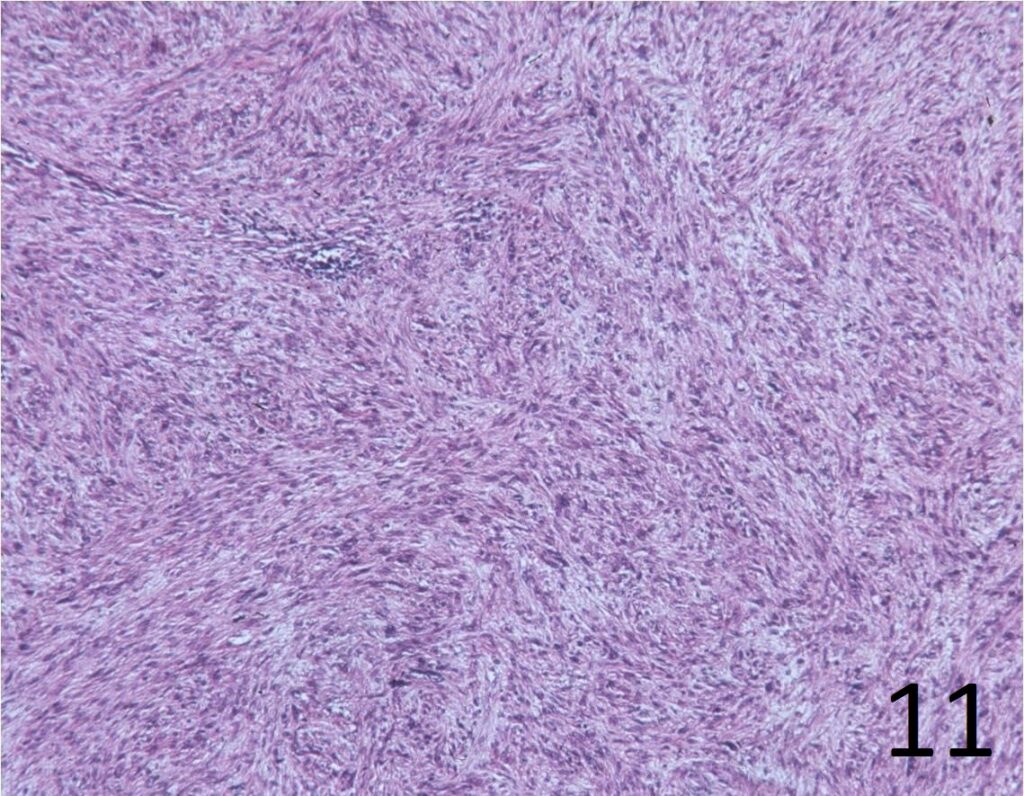

Microscopic

• Elongated, fairly uniform spindle cells with scant cytoplasm in a fibrous stroma

• Large nuclei with abnormal mitoses present; Higher grade tumors have more mitoses, necrosis and pleomorphism.

• Minimal pleomorphism with low grade tumors; More pleomorphism and mitoses with higher grade tumors

• Herringbone pattern (fascicles that intersect at right angles) (Fig. 11)

• Nuclei appear elongated with round ends (Fig. 12)